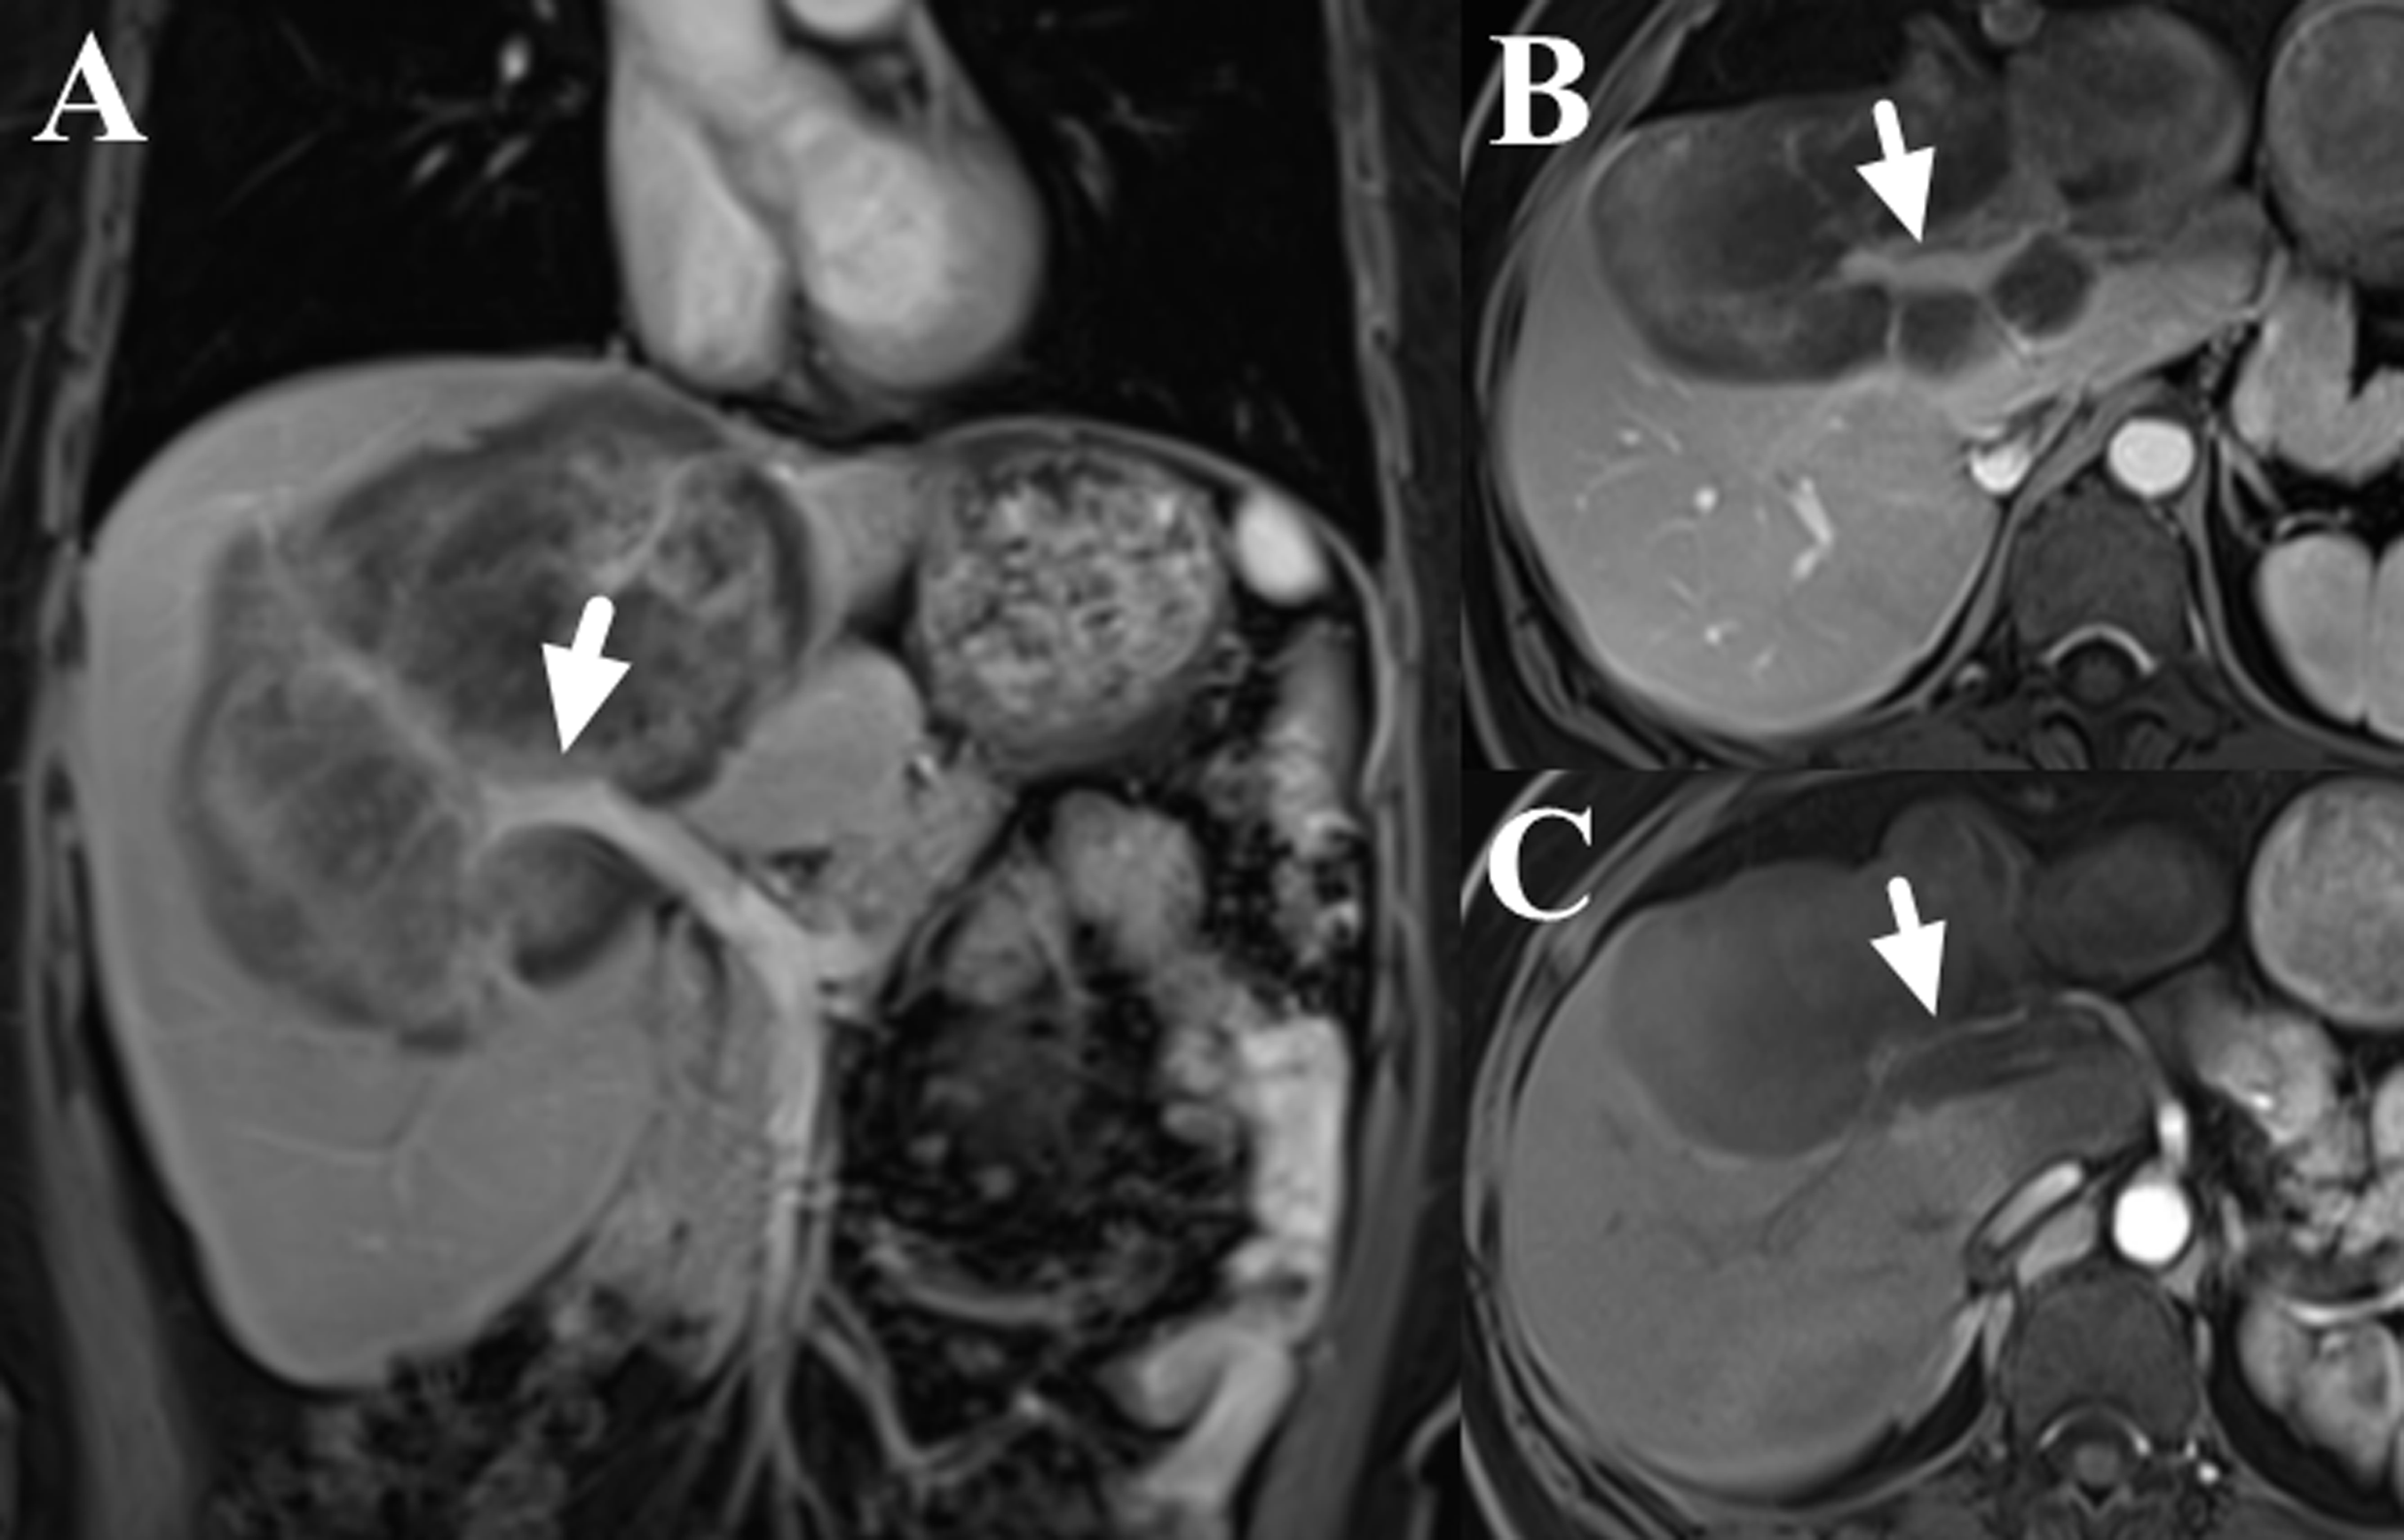

Figure 2

Contrast-enhance images of liver MRI (dose: 0.1 mmol/kg; injection rate: 2.0 ml/s; TR/TE: 3.6/1.7 ms; slice thickness: 5 mm; image matrix: 256 × 192; field of view: 40 × 44 cm; the scanning delay times were 20s, 60s and 180s for the arterial, portal and delay phases, respectively), which showed the involvement of right branch of portal vein (A, B, marked with arrows) and right hepatic artery (C, marked with arrow).